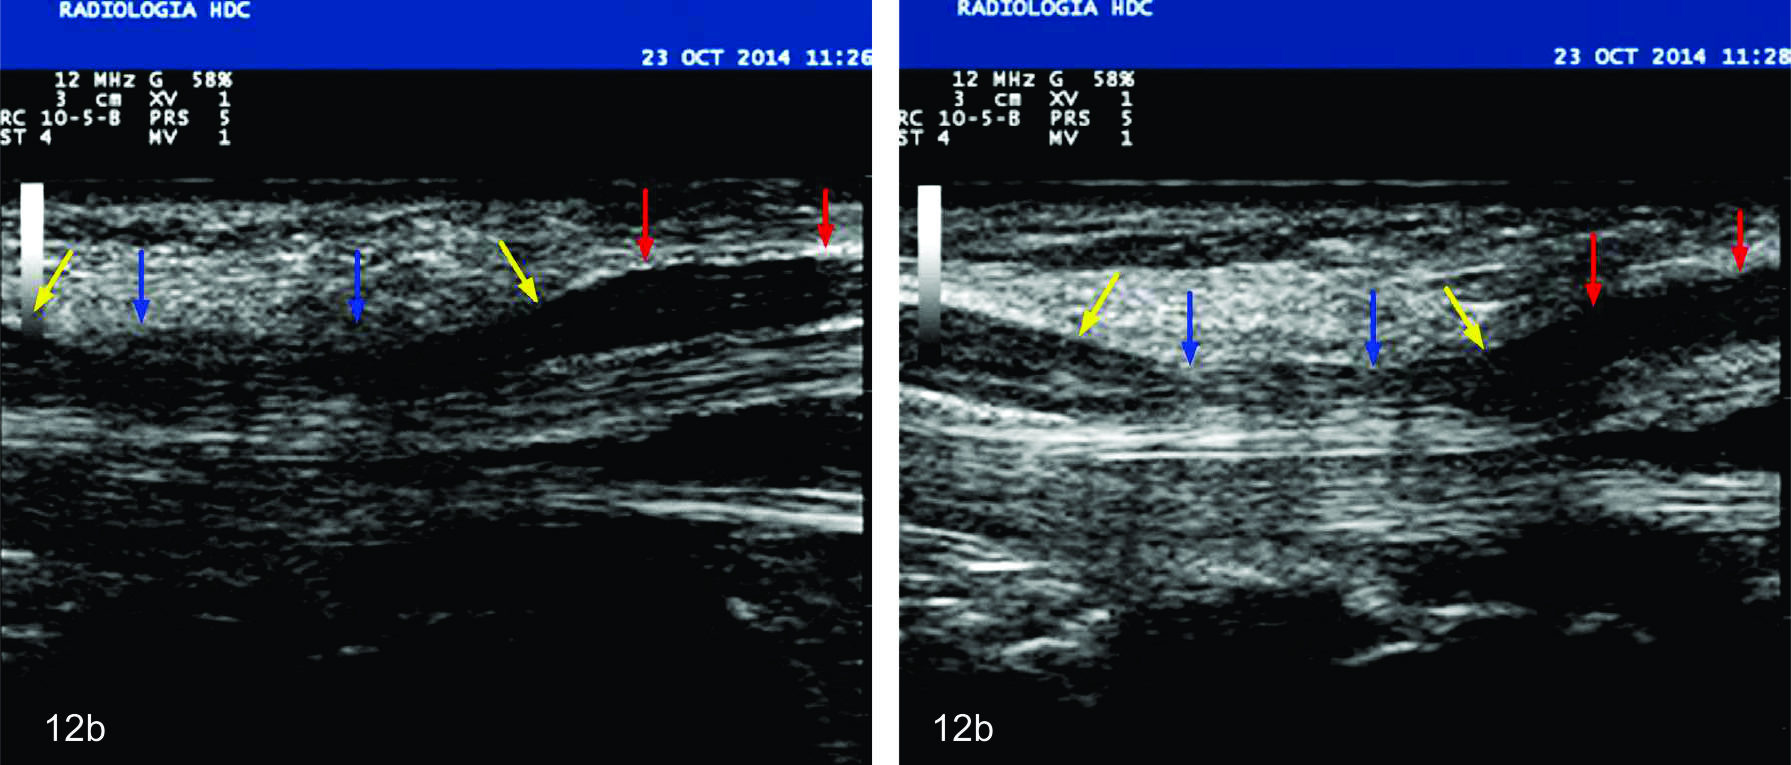

Figura 12 b

Síndrome del túnel carpiano

Se observan dos cortes longitudinales sobre el nervio mediano los cuales demuestran el signo de la muesca. En ambas imágenes, el corte es en la zona del nervio mediano inmediatamente proximal al ingreso al túnel (flechas rojas) donde el nervio se encuentra engrosado e hipoecogénico y en la zona del túnel propiamente (flechas azules) donde el nervio se encuentra achatado y comprimido. Se observa el cambio de calibre brusco o signo de la muesca (flecha amarilla) tanto en el ingreso al túnel como en la salida del mismo.